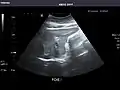

Abdominal ultrasonography (also called abdominal ultrasound imaging or abdominal sonography) is a form of medical ultrasonography (medical application of ultrasound technology) to visualise abdominal anatomical structures. It uses transmission and reflection of ultrasound waves to visualise internal organs through the abdominal wall (with the help of gel, which helps transmission of the sound waves). For this reason, the procedure is also called a transabdominal ultrasound, in contrast to endoscopic ultrasound, the latter combining ultrasound with endoscopy through visualize internal structures from within hollow organs.

Ultrasonography of the kidneys is essential in the diagnosis and management of kidney-related diseases. The kidneys are easily examined, and most pathological changes in the kidneys are distinguishable with ultrasound.[7]